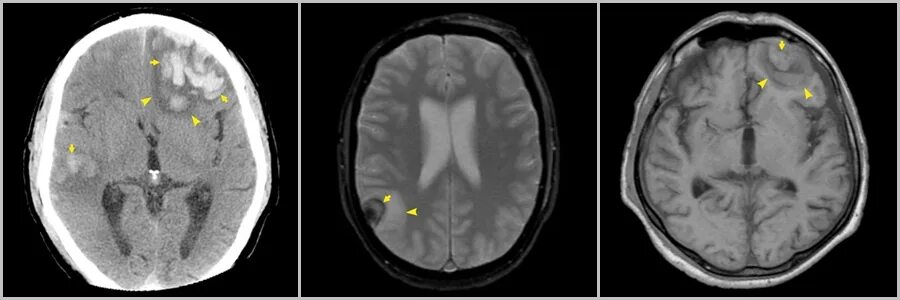

Ушиб мозга на кт